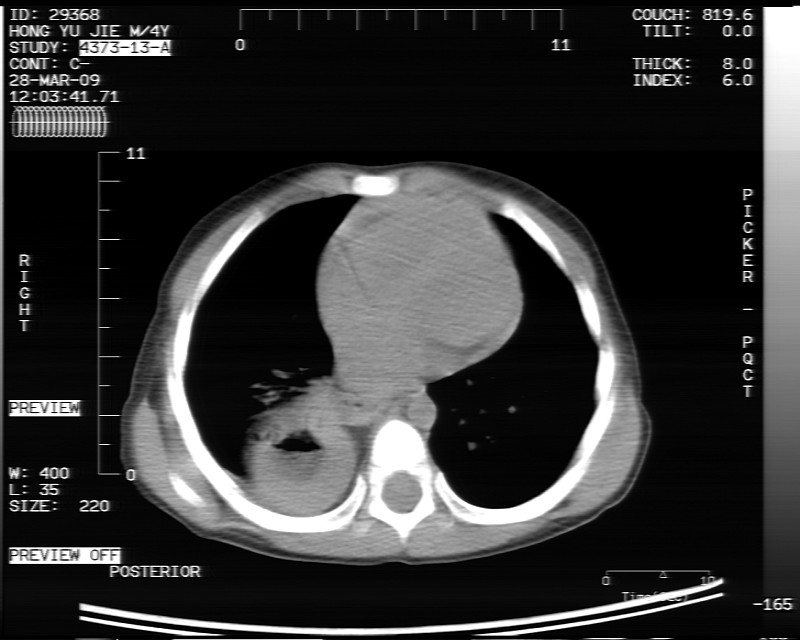

标题: PED1814:胸片体检发现右下肺病变。

男性,3岁,斜疝术前常规检查胸片体检发现右下肺病变。咳嗽,无发烧。

内有气体,液平面,考虑食管裂孔疝可能性大。建议食道钡透。

有液气平面,前部肺纹理聚集(受压改变),周围肺野及相邻胸膜清晰,支持膈疝,可吞服造影剂看一下。

考虑膈疝(右侧胸腹膜裂孔疝?)。